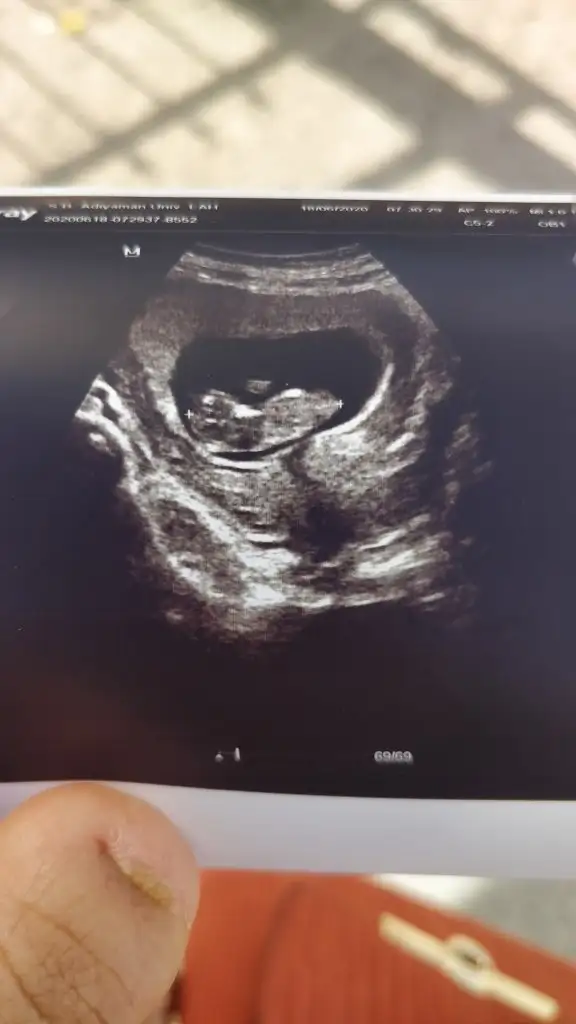

Kese olayı tamamiyle yanlış. Benim birisi yuvarlak birisi uzun muz gibiydi.(ikiz) Biri kız biri oğlan olur diyordum. En başından beri öyleydi. Ama yok kesin ikisi de kızmış :)

Ay ne kadar tatlış maşallah nasılda durmuş tüm resimlere baktım da bu dikkatimi çekti çok güzel durmuş minnacık Allah hayırlısıyla kucağına almayı nasip etsinMeraba arkadaslar benimki içinde tahminde bulunursaniz çok sevinirim 10 haftalik![]()

Erkek gibi geldi bana sizinkiKızlar 6+4 teki ultrason kağıdım kese bildiğin armut gibiydiYorumlayacak olan varmı?

Karından mı canımKizlar banada yorum yaparmisiniz rica etsem6+4 burda